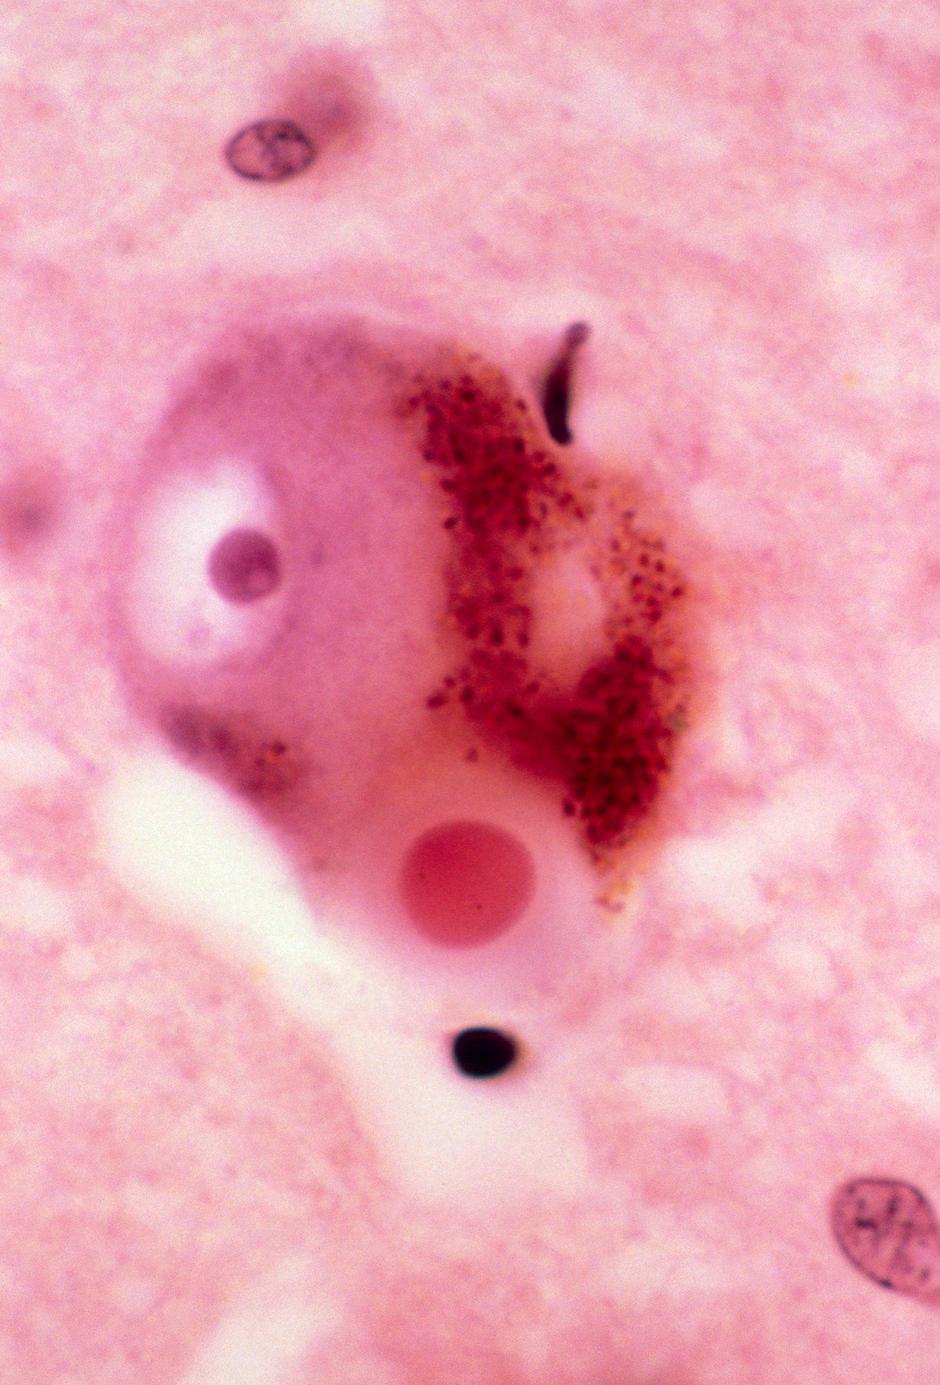

Glavna značilnost bolezni je propadanje dopaminskih nevronov v kompaktni črni substanci, kar pa vodi do pomanjkanja dopamina v možganih. Bolezen se po navadi pojavi pri starosti okoli 60 let in nekoliko pogosteje prizadene moške kot ženske.

Parkinsonova bolezen nastane zaradi motnje v omrežju nigrostriatnih dopaminergičnih nevronov. | Avtor: Profimedia Profimedia